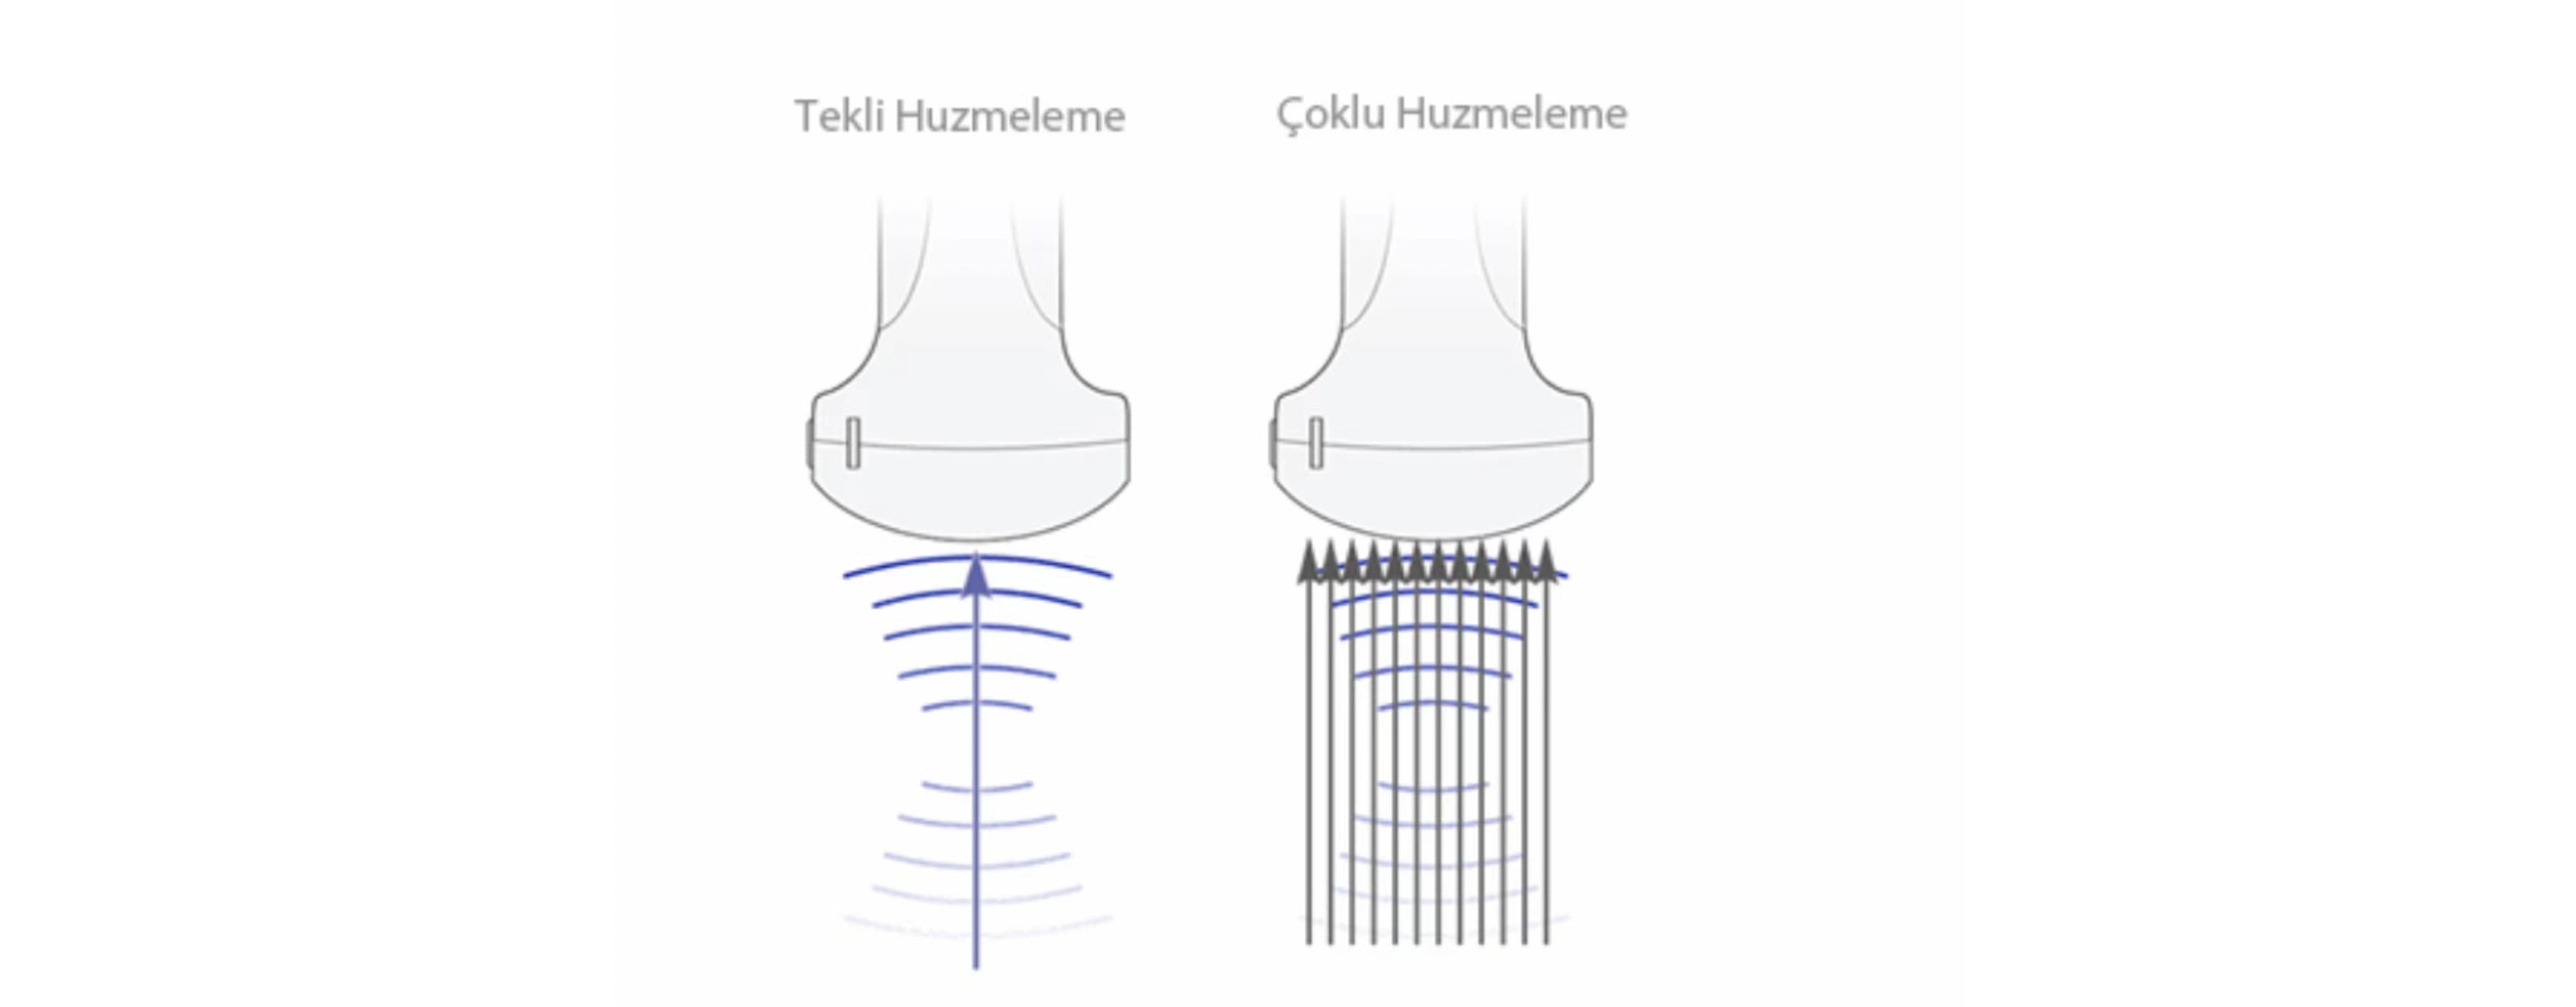

?oklu Huzmeleme

MĂŒkemmel zamanlama ??zĂŒnĂŒrlĂŒ?ĂŒ ve daha yĂŒksek ?er?eve h?z? elde edilen, tek bir aktar?lm?? ???n i?in maksimum 12 defa i?lem sĂŒresi.